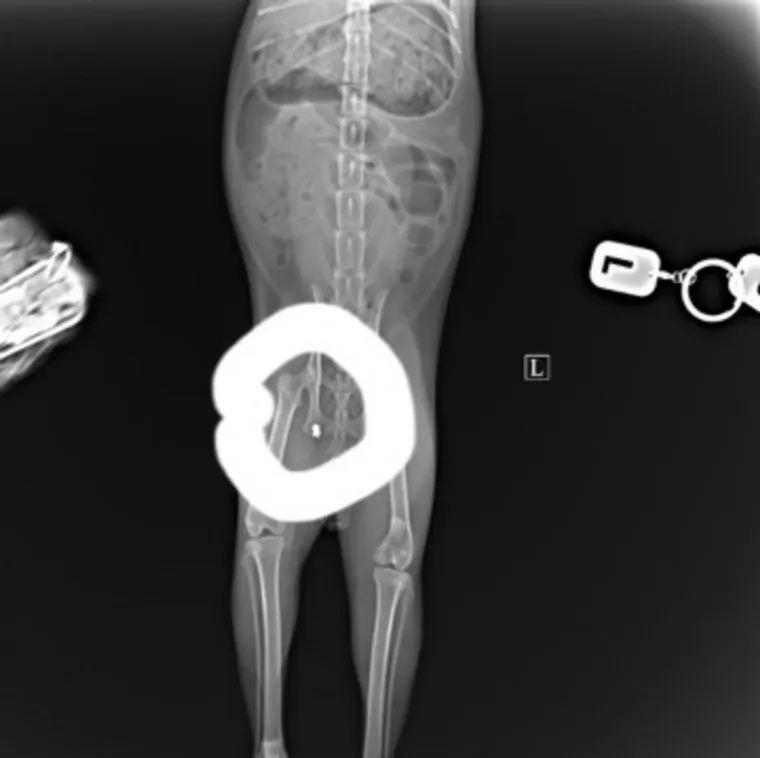

«Возили черного бездомного кота с обрезанными ушами и хвостом на рентген. Пока еще приема не было, по этому поводу и неизвестно есть ли метастазы у трех новообразований. Но стал известен точно один факт. В несчастного кота еще и стреляли — обнаружена пуля в бедре», — пишут волонтеры движения «Подари свою доброту» в соцсети «ВКонтакте».

Пулю обнаружили не сразу

Фото: Фото: сообщество «Подари свою доброту» Волонтерское движение» соцсети «ВКонтакте»